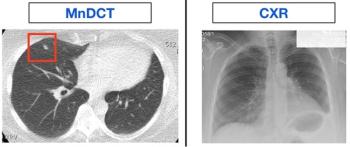

Minimal dose computed tomography finds far more new or recurrent lung cancers than X-ray in patients who had undergone resection of lung cancer.